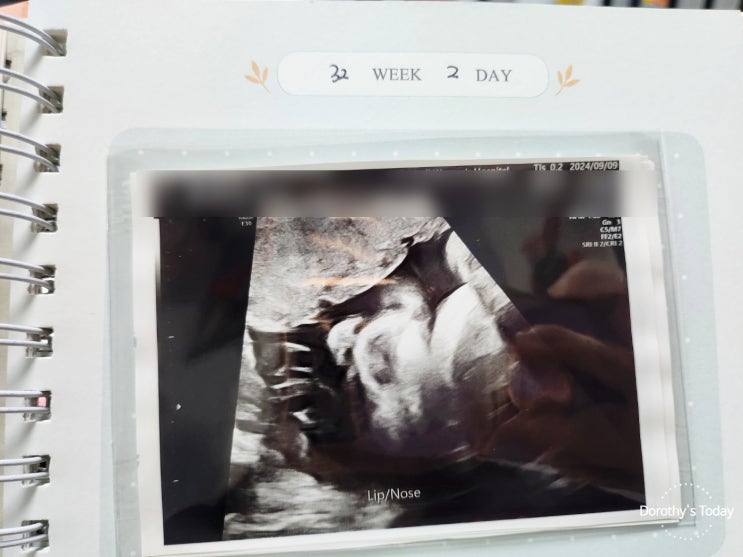

[임신기록] 임신32주차 / 후기정밀초음파

2024. 09. 09 (월) 임신 32주차 후기정밀 초음파 오른손 펀치 왼손 펀치 ㅋㅋㅋ 오늘은 후기 정밀 촘파 날...